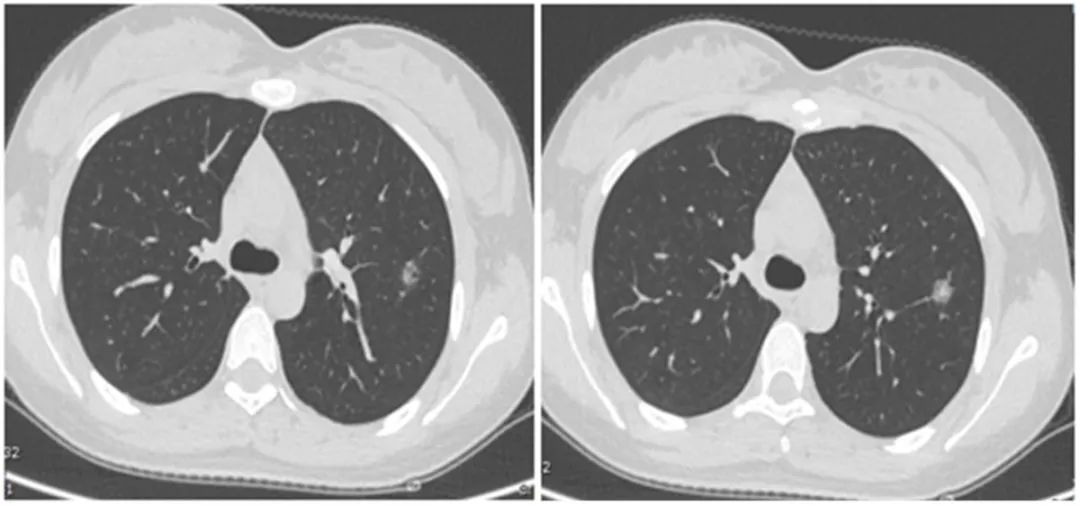

福建省肿瘤医院始终扮演着我省抗癌工作的坚强堡垒角色,并为肿瘤病人提供综合治疗,兜底全省的疑难重症癌症病人诊治工作。近年,医院强化技术创新,建立了各种肿瘤多学科诊疗的技术体系和全疾病周期的健康管理,针对每个病人的不同病情制定个体化诊疗策略,有机地在病人的不同治疗阶段合理使用,最大程度提高远期疗效,同时保障病人的生活质量,延长晚期病人生存期,使更多不可治的肿瘤得到可治。初步统计,2022年相关数据显示,在外院抗肿瘤治疗后转诊至该院进一步治疗的疑难病人治愈及好转率达 45.85%,有效率 96.5%。 当前,全院上下正坚持用党的创新理论武装头脑、指导实践、推动工作,坚持学理论、悟思想,边学习边思考,边检视边整改,切实推动党建和业务工作双融双促,努力在以学铸魂、以学增智、以学正风、以学促干上取得实效。 近期,海都记者走访了省肿瘤医院,通过一个个生动的事例,展现该院是如何让“不可治”的肿瘤变得“可治”。 五十多岁的李先生是一名EGFR突变晚期肺癌患者,经化疗、免疫治疗后,病灶仍增大,且肿瘤对三代EGFR-TKIs产生耐药。一时间乌云笼罩,治疗陷入僵局。 福建省肿瘤医院胸部肿瘤内科何志勇主任团队,针对李先生的情况仔细研究、探讨后,制定了提高三代EGFR-TKI的给药浓度的方案,最终取得令人欣喜的结果,肿瘤明显退缩。目前,李先生仍在维持治疗中,病情稳定,生活质量良好。 据悉,几乎每个EGFR突变晚期肺癌患者都要面临耐药的问题,这类患者的治疗也是目前临床上的难点和热点。福建省肿瘤医院胸部肿瘤内科何志勇主任团队一直在探索研究。 时间拉回到三年前。2019年12月,五十多岁的莆田患者李先生来到福建省肿瘤医院胸部肿瘤内科何志勇主任门诊,他患有EGFR突变晚期肺癌,且往已经接受过多种方案治疗,包括化疗、一代EGFR-TKI治疗24个月、三代EGFR-TKI治疗18个月。 “当时,患者肺部病灶增大,提示肿瘤对三代EGFR-TKI耐药,因仅肺部肿瘤增大,我们建议继续三代EGFR-TKI联合抗血管靶向治疗,患者仍有获益,无进展生存时间9个月。” 何志勇主任介绍说,后来,李先生仍由于肺部病灶的进展接受过多程的化疗联合免疫治疗,期间肺部肿瘤进展缓慢,直至2022年9月,肿瘤又出现快速进展,表现为双肺转移灶增大增多、并新增多发肝转移。 双肺转移灶增大增多,并新增多发肝转移男子接受了多方案治疗肺癌仍在增大并转移

双肺粟粒样转移和肝脏转移明显缩小